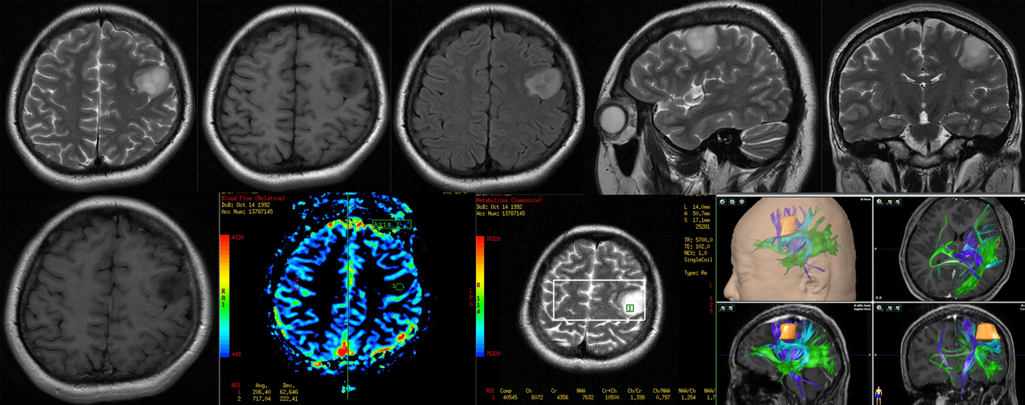

术前磁共振:

肿瘤位于左中央前回中端偏腹侧,长T1长T2,无明显强化,低灌注

唤醒手术最大安全切除左中央区胶质瘤,术中照片:皮层电刺激(2.5mA)定位出患者感觉区感觉区皮质(标志点1小指,2拇指,3口角)和口角运动区(标志点4)以及数数中断并出现口角抽搐癫痫发作(标志点5),其中标志点5在肿瘤表面,肿瘤位于左中央前回腹侧。